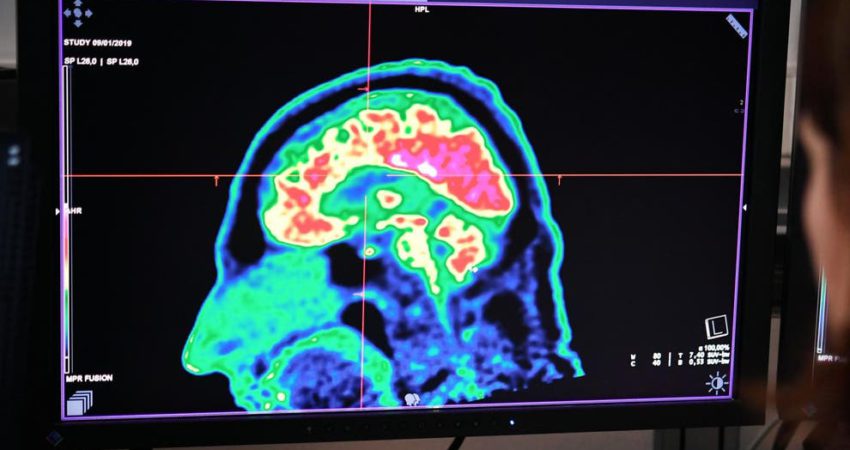

Glioma pontine e përhapur e brendshme (DIPG) është një lloj tumori i rrallë dhe që rritet shpejtë në pjesën ku lidhet shtylla kurrizore me trurin. Fëmijët me DIPG zakonisht pritet të jetojnë vetëm nëntë deri në 12 muaj pas diagnozës së tyre dhe nivelet e mbijetesës nuk janë përmirësuar për 50 vjet.

Tumoret DIPG janë të vështira për t’u hequr në mënyrë kirurgjikale sepse nuk kanë kufij të përcaktuar mirë të përshtatshëm për operim. Një e katërta e fëmijëve me DIPG kanë një mutacion në një gjen të njohur si ACVR1, por nuk ka trajtime të miratuara për këtë gjë.

Në një studim të ri, shkencëtarët në Institutin e Kërkimit të Kancerit, Londër (ICR) dhe fondacioni “Royal Marsden NHS Foundation Trust” ishin në gjendje të përdorin inteligjencën artificiale për të kuptuar se sa e dobishme është të kombinosh ilaçin everolimus me një ilaç kundër kancerit të quajtur vandetanib. Kombinimi është treguar efektiv tek minjtë dhe është testuar fillimisht në katër fëmijë. Studimi tregoi se kombinimi i dy ilaçeve rriti sasinë e vandetanib në trurin e minjve me DIPG me 56 përqind. Trajtimi ishte gjithashtu në gjendje të zgjaste mbijetesën tek minjtë me 14 përqind në krahasim me ata që merrnin një trajtim standard. Ekspertët tani shpresojnë të testojnë kombinimin e ilaçeve në një grup më të gjerë të fëmijëve në provat klinike. Chris Jones, profesor i biologjisë pediatrike të tumorit të trurit në ICR, tha se DIPG është një kancer i rrallë që ka nevojë për të gjetur trajtime të reja për këtë sëmundje.